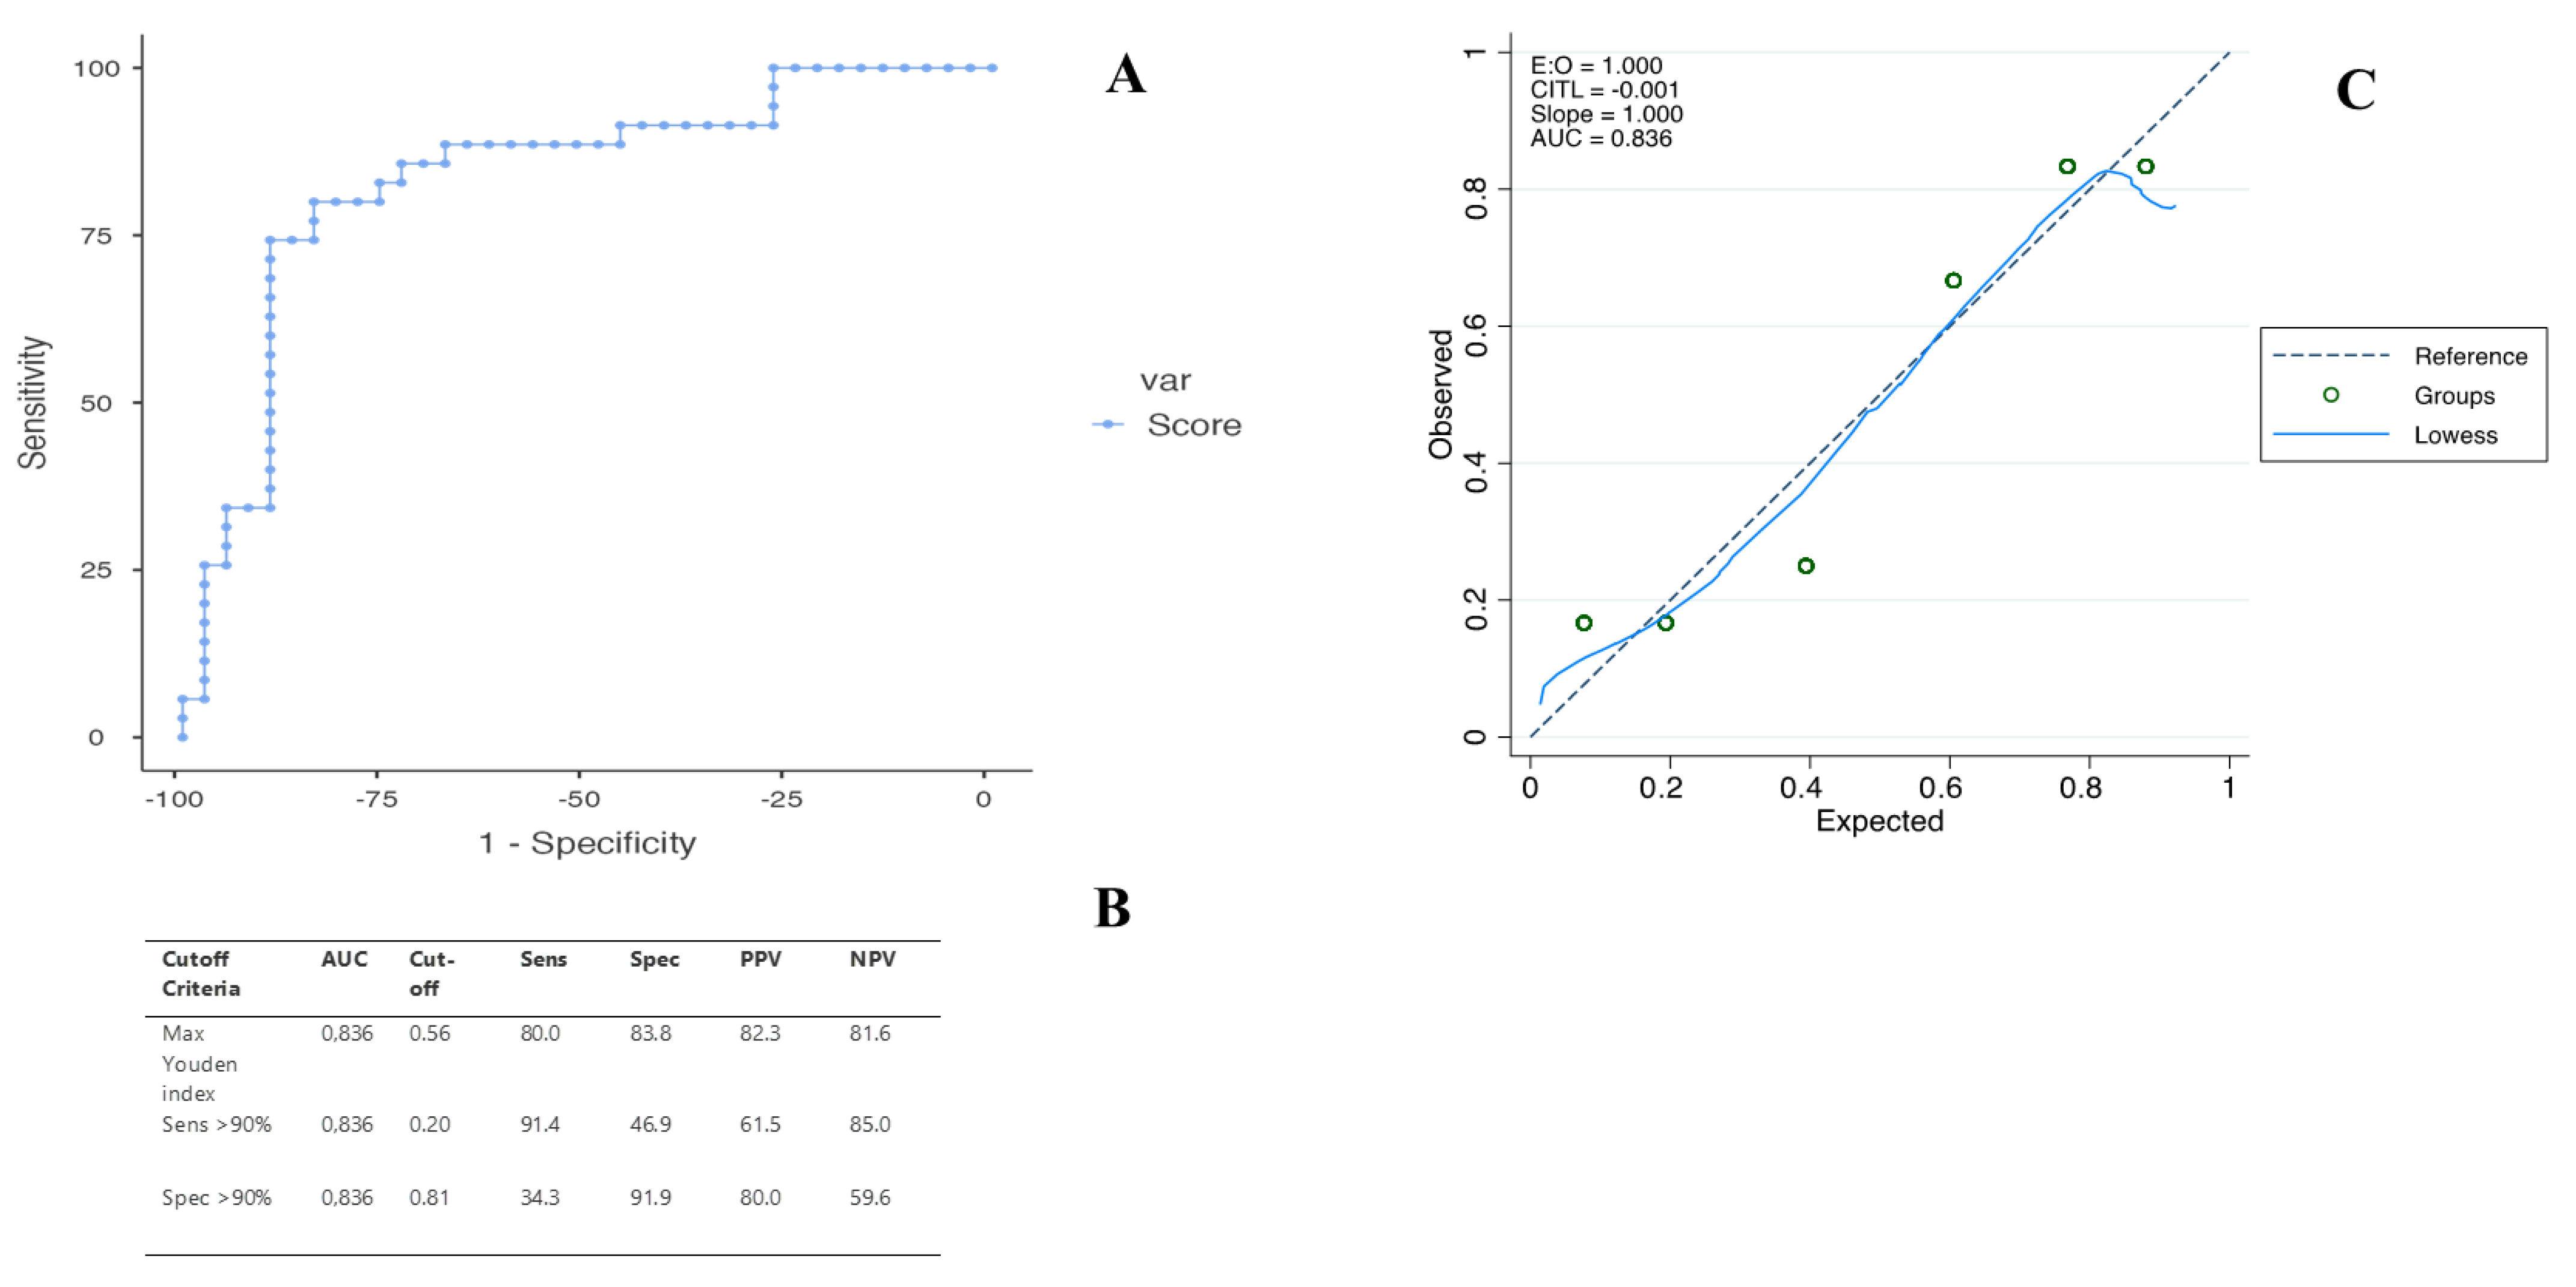

2.3. Diagnostic Performance of the US Score in Predicting ICC